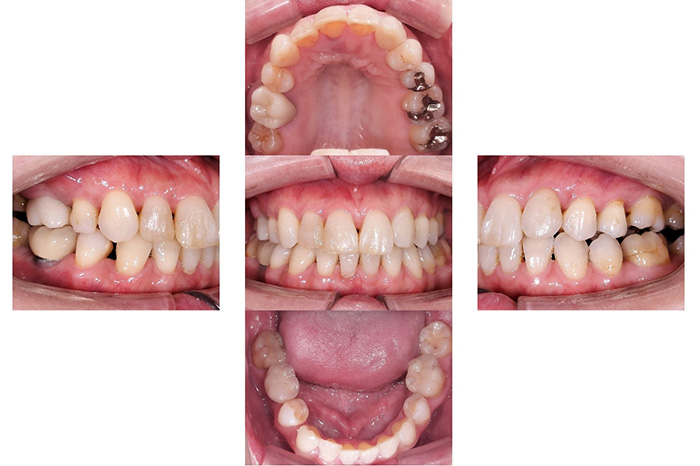

Before

インビザラインによる全体矯正後に補綴治療を行い、咬合と審美性を総合的に改善した症例です。

まずマウスピース型矯正装置(インビザライン)により歯列および咬合関係を整え、その後、必要部位にジルコニア補綴を行いました。

矯正のみ・補綴のみではなく、両治療を組み合わせることで機能性と審美性の両立を目指した包括的治療です。